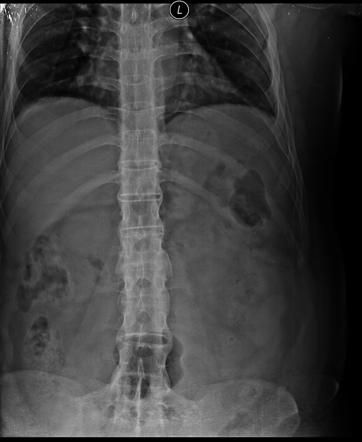

Bamboo Spine on X-ray in a patient with Ankylosing Spondylitis

Rheumatology

X Ray

Spondylitis

Bamboo Spine

Ankylosing